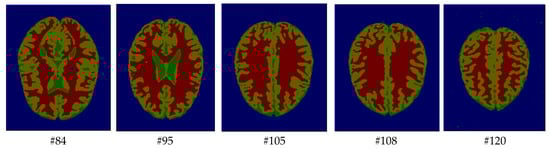

As mentioned before, the images of the first five datasets in Table 3 were used to evaluate the performance of the HMRF-WOA. Figure 1, Figure 2, Figure 3, Figure 4 and Figure 5 show some slices of a T1-weighted image (slices: 84, 95, 105, 108, 120). These brain images correspond to the slices under different types of conditions, such as database type, dimension image, noise level, intensity non-uniformity level, and slice thickness (mm). In Table 1, rows 1 to 5 summarize the parameters of Figure 1, Figure 2, Figure 3, Figure 4 and Figure 5, respectively. Figure 6 represents the ground truth segmentation of slices 84, 95, 105, 108, and 120. In this figure, each column contains the three tissues, GM, WM, and CSF, of each slice. Figure 7, Figure 8, Figure 9, Figure 10 and Figure 11 show the segmentation results, where the four tissues (BG, GM, WM, and CSF) are shown with different colors. The yellow, red, and green colors represent the segmented regions of GM, WM, and CSF, respectively. As we can also see from these figures, the resulting segmented images in Figure 7, Figure 8, Figure 9, Figure 10 and Figure 11 are almost close to the initial images in Figure 1, Figure 2, Figure 3, Figure 4 and Figure 5.

Figure 6. Ground truth segmentation of the GM, WM, and CSF tissues.